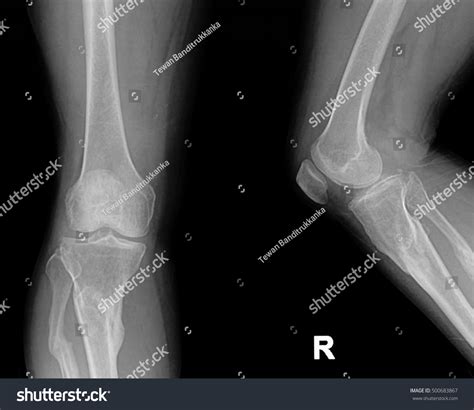

What Does a Normal Knee Xray Look Like?

A radiologist interprets a knee X-ray by looking at several key anatomical landmarks. When a report comes back as a normal knee xray, it means the technician and radiologist have observed the following components as being within standard clinical limits:

• Bone Integrity: There are no visible breaks, hairline fractures, or bony abnormalities.

• Joint Space: The gap between the femur (thigh bone) and the tibia (shin bone) is symmetrical and maintained, which suggests that the articular cartilage has not significantly eroded.

• Alignment: The bones are in their proper anatomical position, indicating there are no major dislocations or congenital malalignments.

• Soft Tissue Shadows: While X-rays are primarily for bones, they can sometimes show swelling or fluid accumulation (effusion) around the knee joint.

Because X-rays primarily capture dense tissue, a "normal" result confirms that the structural framework of your knee is intact. This is excellent news if you were concerned about a broken bone or severe bone deformity.